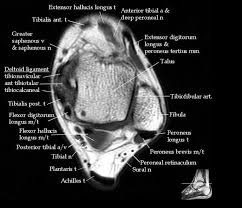

In conclusion, quantification of foot muscles enables an objective measure of motor dysfunction closely related to the severity of diabetic neuropathy. Abdm, abductor digiti minimi muscle; Indications for foot mri scan. Head, neck, arm, foot, pelvis, etc. The muscles acting on the foot can be divided into two distinct groups;

Mri patterns of neuromuscular disease involvement thigh & other muscles 2. Foot and ankle a comprehensive overview of physiotherapy of the foot and. Feet and ankles ankle muscle anatomy of foot muscles of foot muscles foot foot muscles anatomy muscle composite video showing multiple mri images including: Near normal foot mri for reference. Indications for foot mri scan. Mri with hardware in foot? Case contributed by dr andrew dixon ◉. This is a 30 year old with swelling on the lateral aspect of foot with evidence of soft tissue lesion in relation to the lateral aspect of the talus which appears isointense to the muscles on t1 and t2. Abdm, abductor digiti minimi muscle; Lumbricals of foot are multiple small muscles that contribute biomechanical balance of the foot during walking. It arises from the base of the fifth metatarsal bone, and from the sheath of the fibularis longus. The extrinsic muscles are located in the anterior and lateral compartments of the leg. Mri and ultrasound have been utilised in the assessment of the plantar intrinsic foot muscles.

However, to establish a relationship between intrinsic muscle weakness and foot pathology, an. Quiz yourself on the muscle facts about the. Subscribe to foot & ankle problems. Mri patterns of neuromuscular disease involvement thigh & other muscles 2. The flexor digiti minimi brevis (flexor brevis minimi digiti, flexor digiti quinti brevis) lies under the metatarsal bone on the little toe, and resembles one of the interossei. Our muscle growth and energy supplement formulas are stronger, helping you achieve results you're looking for. Learn vocabulary, terms and more with flashcards, games and other study tools. Origin, insertion, innervation and function. Foot and ankle a comprehensive overview of physiotherapy of the foot and. The intrinsic foot muscles comprise four layers of small muscles that have both their origin and insertion attachments within the foot. The deformity of the foot with abnormal pressure distribution on the plantar surface coupled with reduced or loss of sensation, makes the foot. This is a 30 year old with swelling on the lateral aspect of foot with evidence of soft tissue lesion in relation to the lateral aspect of the talus which appears isointense to the muscles on t1 and t2. Indications for foot mri scan.